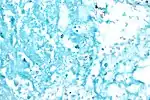

Acid fast bacilli, Ziehl Neelsen stain.